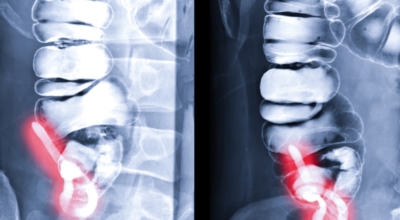

맹장염은 맹장 끝 충수돌기에 나타나는 염증이라고 볼 수 있고, 보통 맹장염으로 알려져 있기는 하나 실질적으로는 부위가 충수돌기이라서 의학 용어로는 충수염이라 하는 단어가 훨씬 정확하다고 합니다. 맹장염(충수염)은 한국 사람들이 수술을 진행하는 질병 5위라고 불릴 만큼 자주 발생하며 해마다 약 10만 명 정도가 수술을 받을 만큼 흔히 나타나는 질환입니다. 복통과 소화불량으로부터 시작하는 맹장염 초기 증상이 발생하는데 많은 분들이 소화기 계통 질환으로 오인해 약만 먹고 그냥 지나치는 경우가 많다고 합니다.

대장이 시작되는 부위를 맹장이라고 하며 그 끝부분에 약 5~10cm 정도의 길이로 꼬리처럼 달린 구조물을 충수 및 충수돌기라고 하는데, 흔하게 말하는 맹장염은 이 충수가 막히거나 눌려서 염증이 발생해 통증이 생기게 되는데 심할 경우 터지는 경우가 발생하기도 합니다.